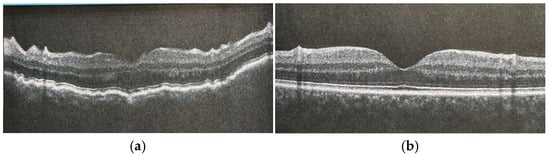

- Martinez de la Casa, J.M.; Feijoó, J.G.; Gómez, A.C.; Benítez, J.M.; Valdizán, C.M.; Sánchez, J.G. Hypotony maculopathy diagnosed by optical coherence tomography. Arch. Soc. Esp. Oftalmol. 2003, 78, 567–569. [Google Scholar]

- Weyll, M.; Gilio, A.; Barbosa, A.; Nicoli, A.A.; Silveira, R.C. Detection of subclinical hypotony maculopathy with OCT III after filtration surgery. Arq. Bras. Oftalmol. 2006, 69, 823–825. [Google Scholar] [CrossRef]